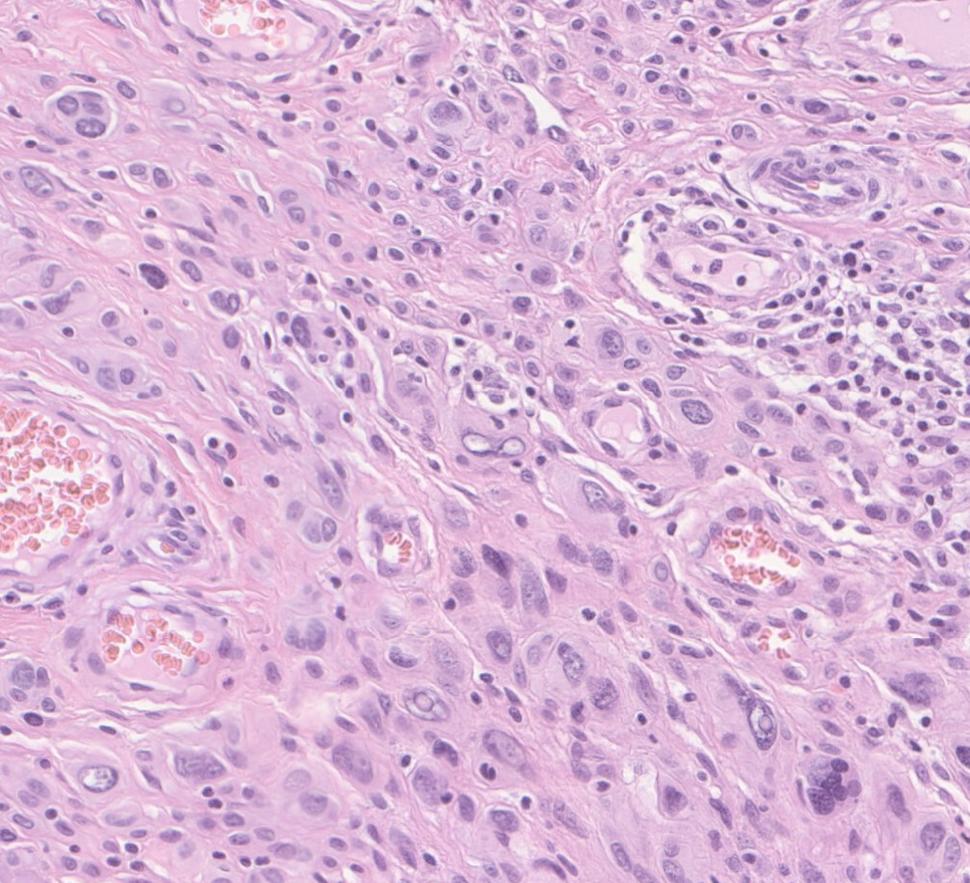

Photo of atypical spitzoid melanoma tissue under a microscope

Atypical spitzoid neoplasm